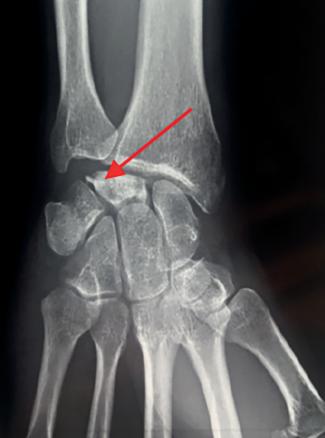

La maladie de Kienböck est une affection rare correspondant à une nécrose (dévitalisation) d’un des 8 os du carpe : le lunatum (fig. 2). On parle aussi de nécrose aseptique du semi-lunaire ou encore lunatomalacie. Cette pathologie atteint plus souvent les hommes (7/1) âgés de 20 à 40 ans.